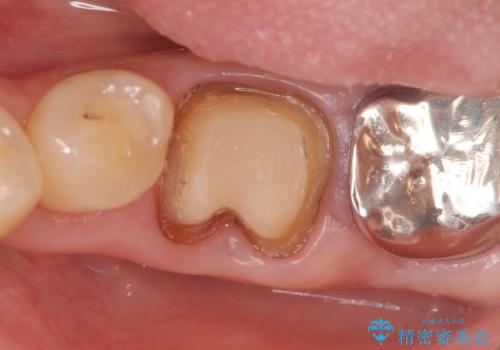

- 左下の銀歯が外れたので診て欲しいといらっしゃった方の症例です。

他院にて再装着したが不安なので、根管治療からやり直したいとのことでした。

再根管治療終了後、オールセラミッククラウンによる補綴を行いました。